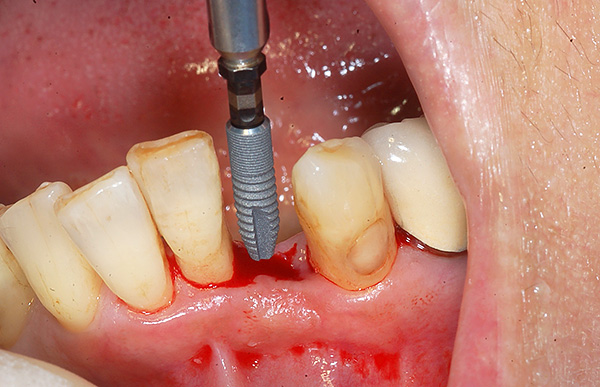

Se c'è un dente permanente nell'osso, ma ha poco spazio per l'eruzione, o è troppo profondo, o si trova nella posizione sbagliata, quindi dopo aver fissato il sistema di staffe e creato un posto per il dente desiderato, il dente viene gradualmente “estratto” dal chirurgo, fissandolo su di esso, prima, il pulsante ortodontico, quindi legandolo all'arco ortodontico.